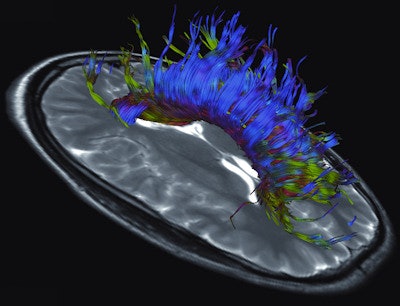

The system also offers a tandem configuration unavailable in any other commercial whole-body system, according to the vendor. The device's combination of high gradient strength and fast gradient switching speed allows for increased image quality compared with conventional devices. Due to this combination of high spatial and temporal resolution, the new machine can reportedly achieve good image quality, especially in very demanding applications. Furthermore, by combining high gradient strength with fast gradient switching speed, the Magnetom Prisma offers new possibilities in areas such as diffusion imaging, because even minor diffusion effects can be captured. Moreover, the diffusion spectrum imaging (DSI) application makes it possible to resolve fine anatomical details of the brain, such as crossing white-matter fibers by using up to 514 diffusion encoding directions, Siemens stated.